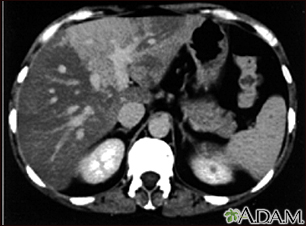

Liver with disproportional fattening - CT scan